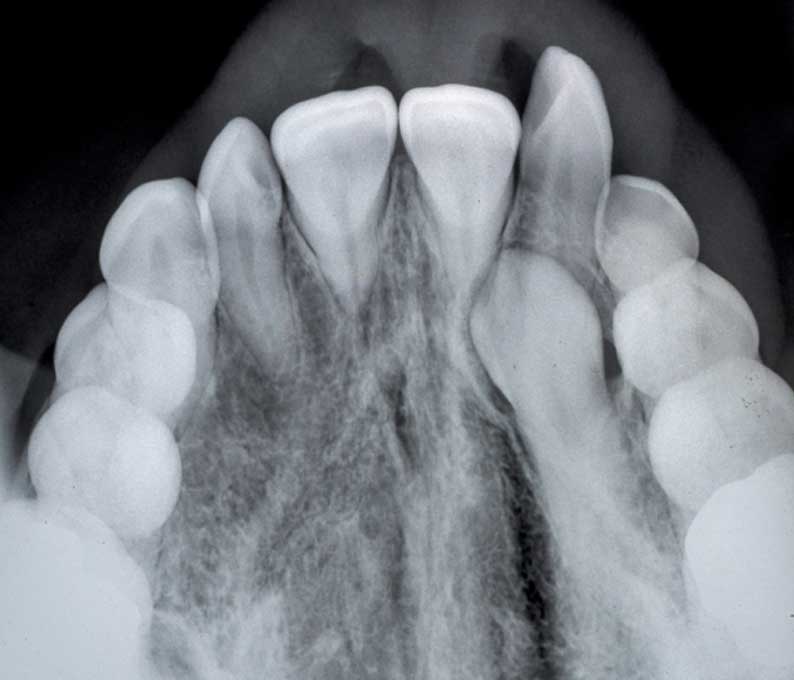

When a tooth remains trapped beneath the gum line, it is considered impacted. Impacted tooth extraction is a surgical procedure to remove the affected tooth and prevent complications such as infection, pain, and damage to surrounding teeth.

In cases where a tooth is stuck beneath the gums, surgical exposure helps guide the tooth into its proper position. This is commonly performed as part of orthodontic treatment to align impacted teeth properly.